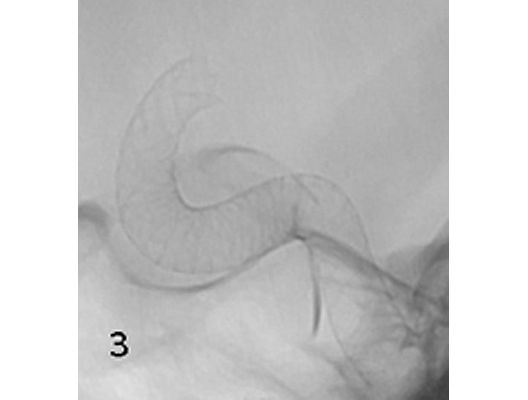

Das Beispiel zeigt die angiographischen Bilder einer Patientin, bei der es zu einer Sehstörung gekommen war. Die Ursache war ein großes Aneurysma der Halsschlagader an der Schädelbasis (Bild 1). Bild 2 zeigt die Lage des Aneurysmas hinter dem Auge. Durch den Druck des Aneurysmas auf den Sehnerv war es zu der Sehstörung gekommen. Die Patientin wurde mit einer speziellen Gefäßprothese versorgt, welche über eine Punktion der Leistenarterie in die Halsschlagader eingesetzt wurde (Bild 3). Bei der Kontrolle nach 6 Monaten zeigte sich ein vollständiger Verschluss des Aneurysmas (Bild 4). Die Sehstörung hatte sich vollständig zurückgebildet.